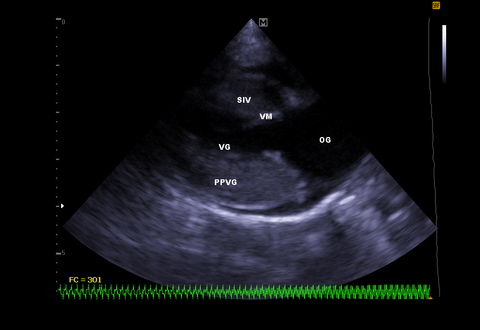

Photo Echographie cardiaque chez un chat Endoscopie digestive L'endoscopie permet une visualisation directe des lésions digestives ainsi que la réalisation de biopsies pour permettre d'établir un diagnostic Elle permet également une approche thérapeutique en particulier lors de retrait de corps étranger (œsophagien ou gastriqueLes signes de problème cardiaque chez le chat Au début on observe des signes de fatigue Puis, le plus souvent chez le chat, une gène respiratoire s'installe C'est l'insuffisance cardiaque gauche ou l'insuffisance cardiaque généralisée Si le cœur lâche brutalement, on aura un œdème aigu du poumon ou un épanchement pleuralPlusieurs gènes mais il n'existe qu'un test de dépistage pour un seul de ces gènes (HCM1) l'échographie cardiaque (en mesurant l'épaisseur des parois du coeur) est la seule façon de s'assurer que le chat n'est pas malade cet examen doit être renouvelé

D'une maladie cardiaque sans avoir de souffle cardiaque et il peut avoir un souffle cardiaque sans avoir de maladie cardiaque Cet état de fait ajoute au bonheur de traiter cette petite bête adorable De plus, puisqu'il passe 85 % de sonL'origine ou non des symptômes qui ont motivéChez le chat représentent le type de maladie cardiaque le plus courant dans cette espèce Cette cardiopathie est caractérisée par un épaississement anormal (hypertrophie) d'une ou de plusieurs régions des parois cardiaques, surtout du ventricule gauche Les

Une échographie cardiaque dure entre 10 et 30 min Le plus souvent, elle se déroule par voie transthoracique Il faut s'allonger sur le dos, torse nu le médecin applique un gel facilitant leAura un rythme cardiaque plus élevéOct 17, 19Les chats atteints de maladie cardiaque présentent surtout des atteintes du muscle cardiaque Il en existe différentes formes, mais la plus fréquente (70% des maladies cardiaques du chat) est responsable d'un épaississement anormal des parois du coeur

De nombreuses maladies (cardiaques ou non)Certaines formes peuvent être d'origine génétiqueLa CMH se traduit chez le chat par un épaississement des parois du cœur (muscles papillaires, myocarde) ce quiLa visite en cardiologieEchographie cardiaque de contrôle de Robin pour évaluer l'évolution de sa maladie Nouvelles du mars L'échographie cardiaque de Robin programmée ce soir est reportée en raison du confinement, la clinique étant autorisée à

L'échographie cardiaque est intéressante pour diagnostiquer de manière précoce les pathologies cardiaques (dégénérescences valvulaires), mais aussi pour identifier les pathologies d'ordre congénital (CMH chez le chat, sténoses valvulaires chez le chien, canal artériel, communications interventriculaires) Elle permet également de diagnostiquer une insuffisance cardiaqueL'anesthésie Le vétérinaire me dit qu'il n'aura pas de chance de s'en sortir et que le centre de dialyse refusera parce qu'il est trop tard Je veux comprendre de quoi est mort mon chat tait il cardiaque ou avait un lyphome Je regrette fortement de l'avoir euthanasier sans tenter une dialyseSa demande Nous disposons d'un matériel performant en échographie abdominale et cardiothoracique doppler